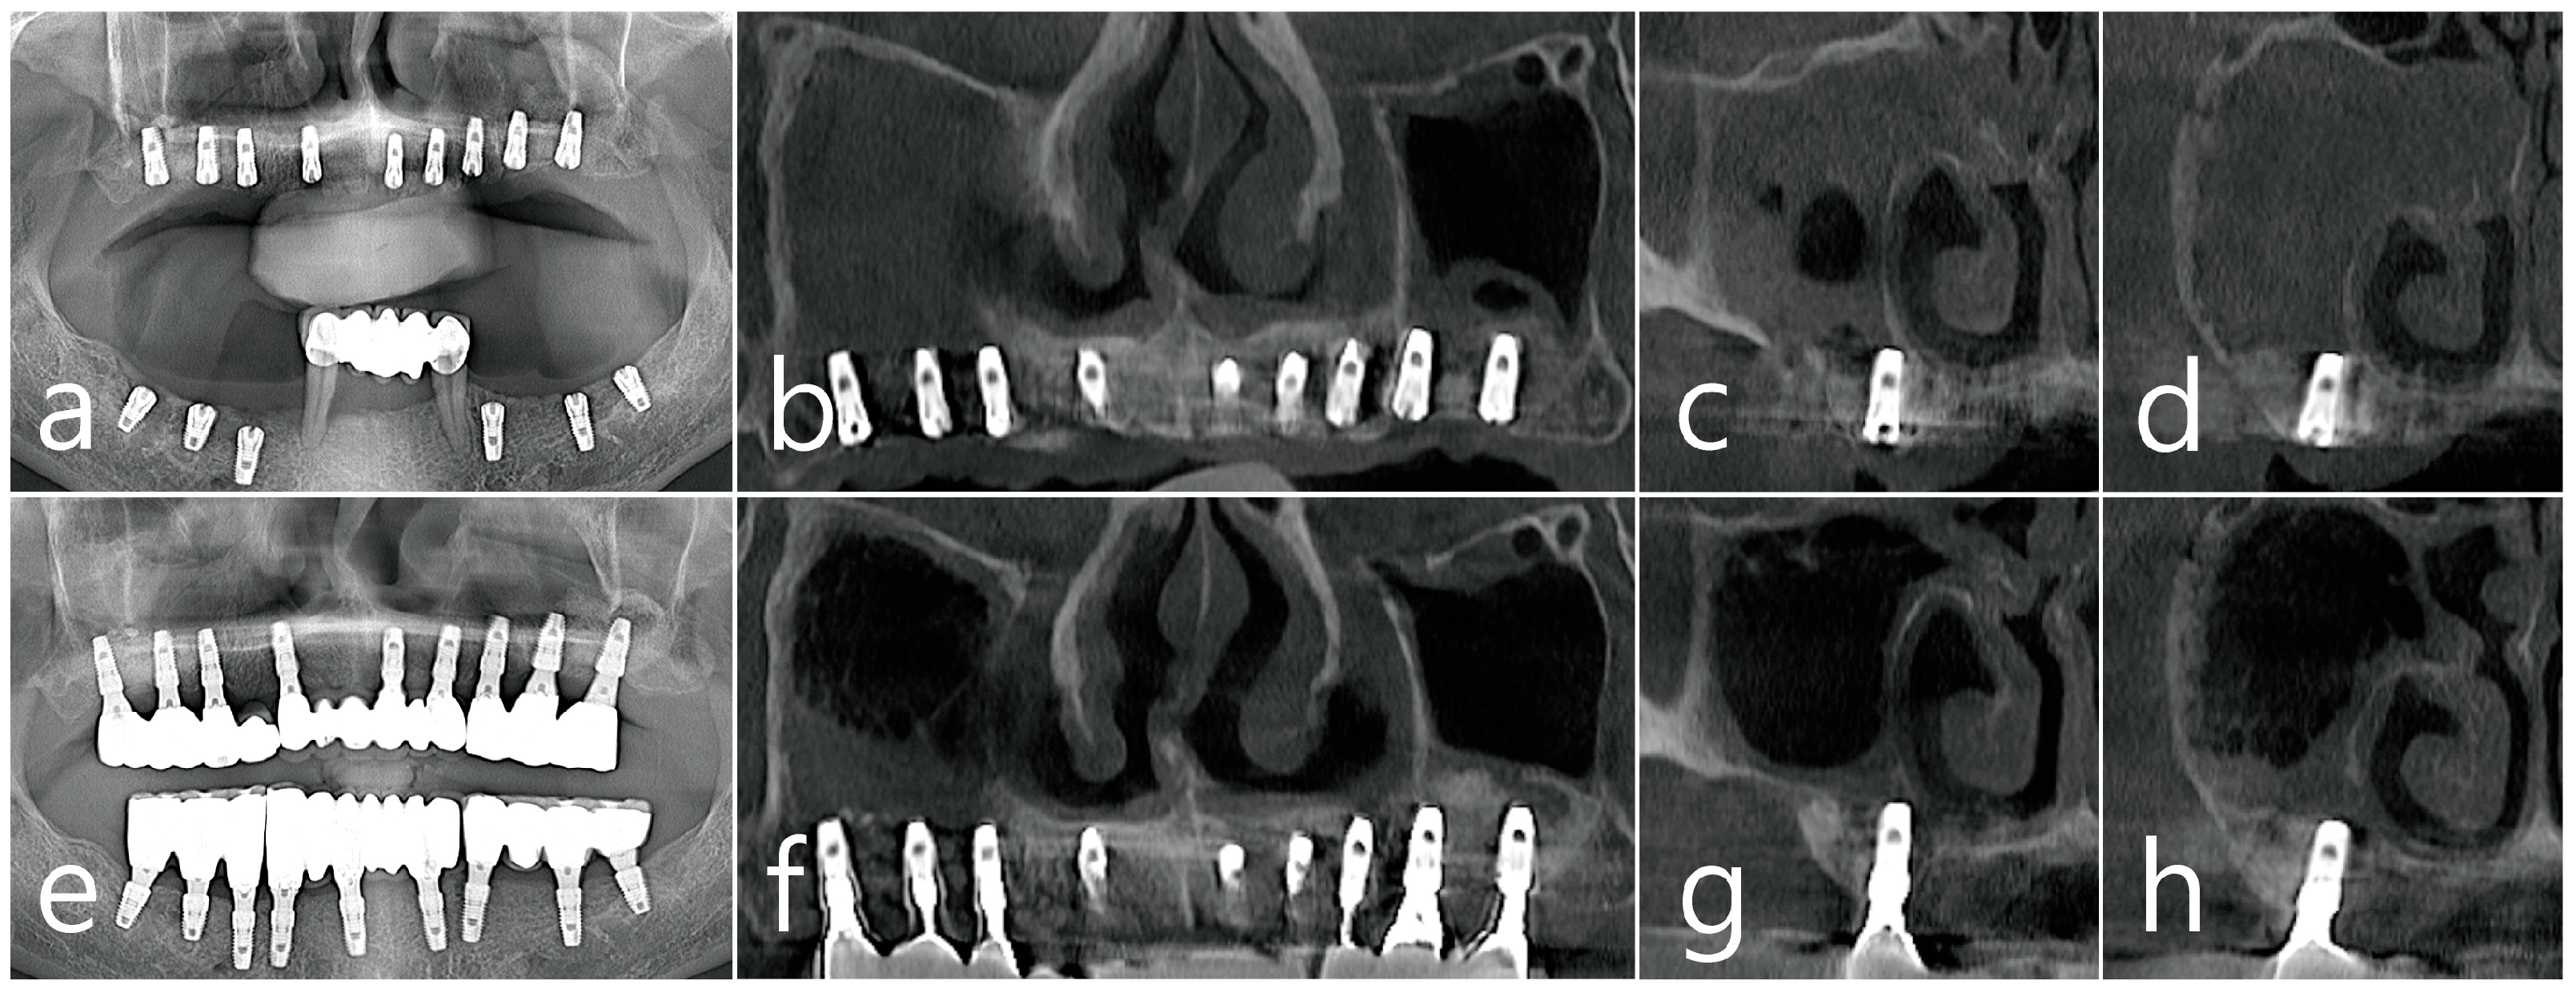

2.1. Case 1

2.2. Case 2